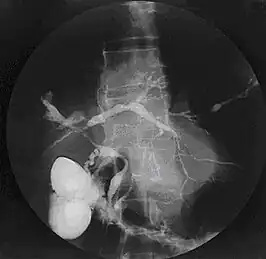

Cholangiogram van primaire scleroserende cholangitis.